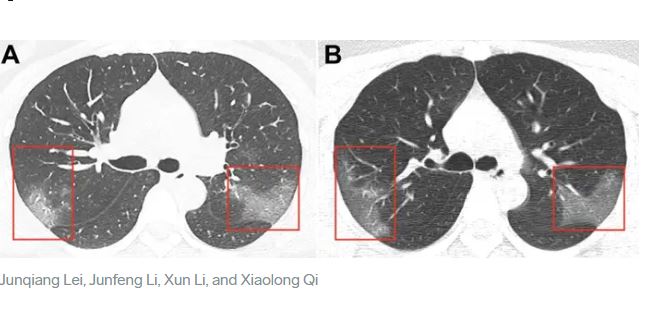

وأوضحت “أشعة إكس” تأثير فيروس كورونا على رئة المُصاب به، حيث بدت الرئتان متورمتان وممتلئتان بالسوائل، وبينت الأشعة “A” وجود بقع بيضاء على الركنين السفليين من الرئتين أطلق عليها الأطباء اسم “ground glass opacity” وهذا يعني أن الحويصلات الهوائية الدقيقة في الرئتين- والتي تُمرر الأكسجين من الهواء إلى الدم- ممتلئة بالماء، الأمر الذي يُسبب شعوراً بالاختناق.

وفي الأشعة “B” التي تصور حالة الرئة بعد 3 أيام من من الأشعة الأولى “A” ازدادت الحالة سوءاً، بازدياد البقع البيضاء، على الرغم من تناول العلاج، حسب ما ورد في صحيفة “دايلي ميل” البريطانية.